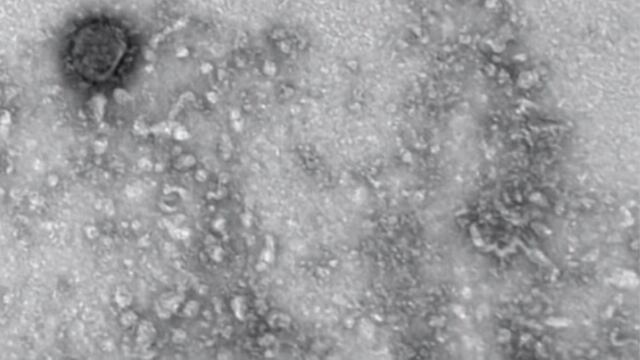

Como un esfuerzo más para comprender cómo funciona, se reproduce e interactúa el virus causante de la Covid-19, los científicos de distintos países están estudiando cada aspecto del virus; por su parte, el Instituto Vector de Novosibirsk de Rusia, difundió las que podrían ser las primeras imágenes del coronavirus que brotó en Wuhan, a través de un microscopio.

El pasado 19 de marzo los científicos mostraron al mundo, una serie de imágenes tomadas a través de un microscopio del nuevo coronavirus y detallaron que este tiene un tamaño de entre 100 y 120 nanómetros.

Sólo para darse una idea del tamaño que tiene el SARS-CoV-2, causante de la enfermedad Covid-19, hay que decir que una célula mide aproximadamente 12.75 micrómetros, o sea, 12 mil 750 nanómetros.